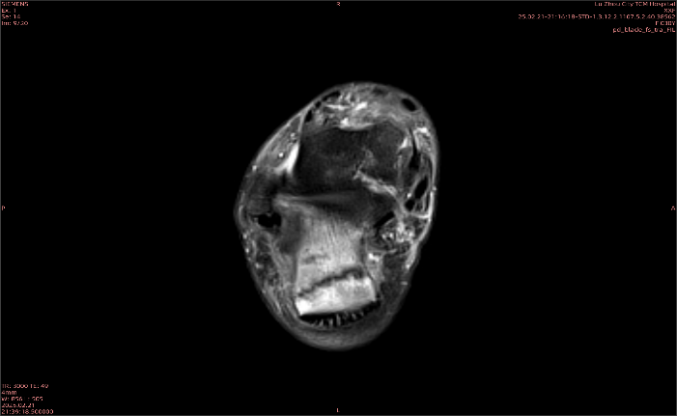

隱性骨折在MRI表現(xiàn)為T1WI序列上見由關(guān)節(jié)面向骨干走行的形態(tài)各異低信號區(qū),有線狀、條狀、紊亂低信號,信號強(qiáng)度不均勻。與T1WI低信號改變相對應(yīng)部位在T2WI上表現(xiàn)為相應(yīng)形狀的高、低混雜信號,且部分低信號周圍可見高信號水腫改變。STIR序列圖像上病灶呈顯著高信號,與信號被抑制的臨近正常骨髓形成鮮明對比,分界也較T2WI成像更為清楚。脂肪組織抑制技術(shù)是MRI的一個(gè)重要性能,脂肪抑制技術(shù)在MRI應(yīng)用中可以改善組織對比和增加病變顯示機(jī)會,這樣骨髓的脂肪抑制后就不會有任何信號,而隱性骨折線及骨髓水腫的異常高信號就會更加明顯的顯示出來。

舉例圖像

圖1

專業(yè)解釋看不懂沒關(guān)系,大家看圖1和圖2就可以了,這是同一個(gè)患者跟骨的磁共振和CT圖像,圖1的紅色箭頭指示的黑線就是磁共振圖像顯示的骨折線,一目了然。而對比圖2的CT圖像上并未顯示異常。

這下大家明白了吧,如果懷疑隱匿性骨折優(yōu)先選擇磁共振檢查